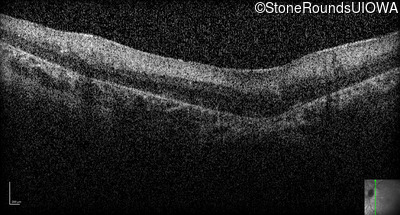

Optical Coherence Tomography - Left -

No Light Perception

Exemplar

Expanded OCT Stack

×